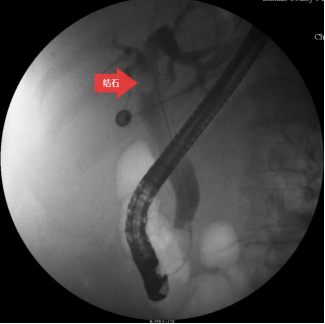

图三:胆道造影

第三步:插管成功后,注入造影剂,造影显示胆总管结石。(箭头所指为胆总管结石)